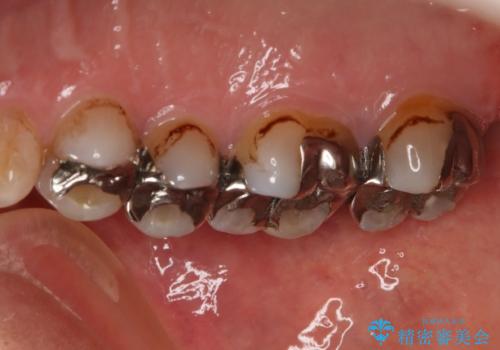

- かなり昔に入れた銀歯の部分のチェックをご希望でご来院されました。

上下ともに銀歯が多く入っており、その下に虫歯が疑われる状態でした。

詰め物の大きさや虫歯の状態から個々に材料と治療範囲を決定し治療に入りました。